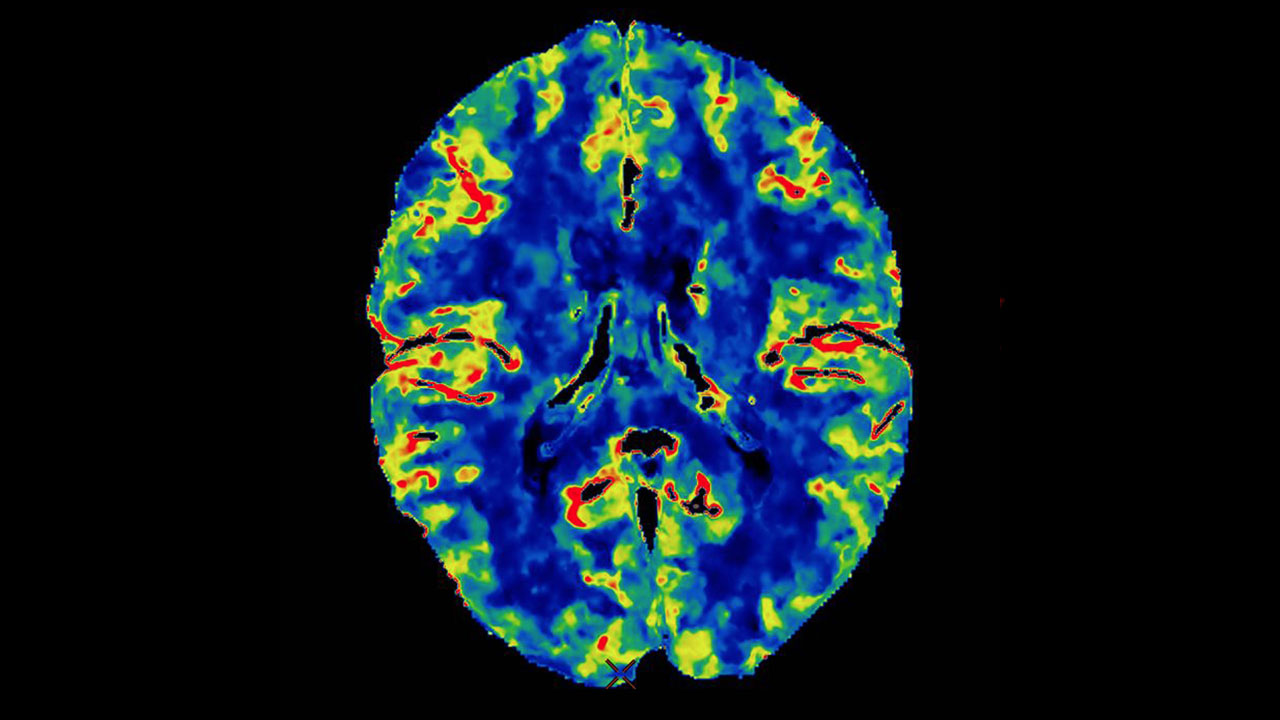

Мр перфузия

Мр перфузия 119 фотографий